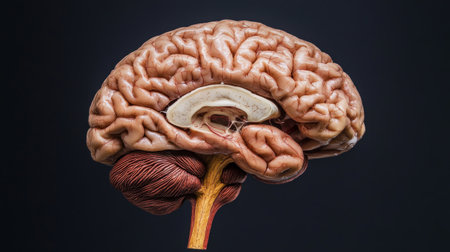

This detailed cross-section of the human brain illustrates its anatomical features, making it ideal for educational purposes in neuroscience and medicine.

This high-quality image features an anatomically accurate brain model, showcasing intricate vascular structures and the spinal cord, ideal for educational use.